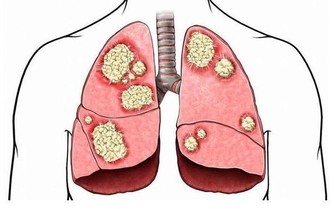

在我國自古就有“喜傷心”、“怒傷肝”、“思傷脾”、“憂傷肺”、“恐傷腎”的說法。

壓抑導致哮喘;經常憤怒的人容易有口臭,還愛發生膿腫;恐懼會引發暈車和痛經。

充滿心理矛盾、壓抑,經常感到不安全和不愉快的人,免疫力低下,經常感冒、一著急就喉嚨痛;緊張的人則會頭痛、血壓升高,容易引發心血管疾病;經常忍氣吞聲的人得癌症的機率是一般人的三倍。